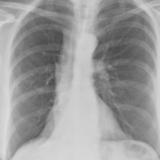

Mass RLL collapse 5 PA

Date: 03/02/2006

Views: 3932